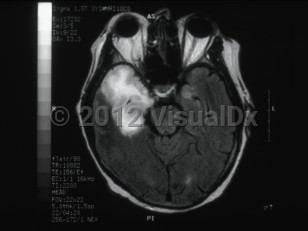

Clinically, patients typically present with focal neurologic signs that have been present for <1 week. In most cases of HSV encephalitis, the temporal lobe of the brain, usually unilateral, undergoes necrosis, and clinical findings reflect the areas of the brain that are affected. They include altered levels of consciousness, behavioral changes, focal cranial nerve deficits, ataxia, aphasia, and seizures. The majority of patients will also present with fever. The behavioral changes most commonly associated with HSV encephalitis are hypomania (including elevated mood, excessive animation, hypersexuality, and decreased sleep requirements), amnesia, and Klüver-Bucy syndrome, which is a behavioral syndrome that involves loss of typical anger and fear responses and increased sexuality. The Klüver-Bucy syndrome is thought to be associated with the proclivity of HSV encephalitis for the temporal lobes and limbic system structures. More rarely, HSV encephalitis can present as a brainstem syndrome and can result in the syndrome of inappropriate antidiuretic hormone secretion (SIADH).